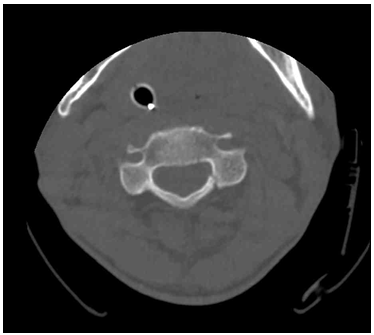

51세 남자가 1시간 전에 계단에서 넘어진 후 의식이 혼미해져 응급실로 왔다. 혈압 48/28 mmHg, 맥박 116회/분, 호흡 14회/분, 체온 36.7°C이다. 피부와 팔다리에 외상의 흔적은 없으며 복부 초음파검사에서 특이 소견은 없다. 검사 결과는 다음과 같다. 수액과 혈관수축제 투여 후 혈압이 안정되어 시행한 목 컴퓨터단층촬영 사진이다. 진단은?

CT: Cervical vertebra Lt. lamina fracture

Neck CT에서 경추의 Lt. lamina fracture가 확인되므로 척수 손상에 의해 증상이 발생한 것임을 알 수 있다. 특히 ABGA상 호흡성 산증 소견이 확인되는데, 이는 호흡 중추나 횡격막 신경이 위치한 C3-5 부위의 손상으로 인해 발생한 것으로 추정된다.

• 따라서 정상적으로 조절되지 않는 혈압, 호흡 등 자율신경계 이상과 함께 경추의 lamina fracture를 확인했으므로 신경성 쇼크를 진단할 수 있다.